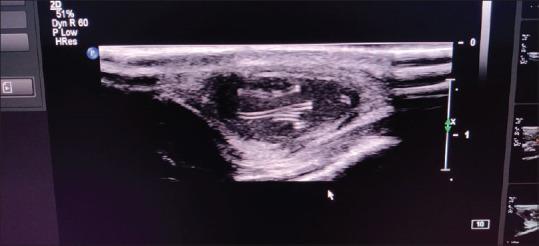

Filariasis caused by nematodes affects the structure and function of lymphatic vessels. Lymphedema due to lymphatic blockage and lymphadenitis is the usual mode of presentation of filariasis. However, rarely extralymphatic filariasis has been reported in uncommon sites, including skin and soft tissue. is the most common nematode causing extralymphatic filariasis. We report a rare case of a 25-year-old man with live extralymphatic filarial infestation presenting as a facial subcutaneous soft-tissue swelling confirmed by ultrasonography (USG), which revealed the filarial dance sign. Filariasis can present in many different ways and pose a significant dilemma for the clinician. It is essential to be aware of atypical presentations of filariasis for prompt diagnosis and further treatment.

由线虫引起的丝虫病会影响淋巴管的结构和功能。因淋巴阻塞和淋巴结炎导致的淋巴水肿是丝虫病常见的表现形式。然而,罕见的是,曾有报道称丝虫病会出现在包括皮肤和软组织在内的不常见部位,即发生在淋巴系统以外。班氏丝虫是导致淋巴系统外丝虫病最常见的线虫。我们报告了一例罕见病例,一名25岁男性患有活的淋巴系统外丝虫感染,表现为面部皮下软组织肿胀,超声检查(USG)确诊,该检查显示了丝虫舞动征。丝虫病可以有多种不同的表现形式,给临床医生带来重大难题。了解丝虫病的非典型表现对于及时诊断和进一步治疗至关重要。